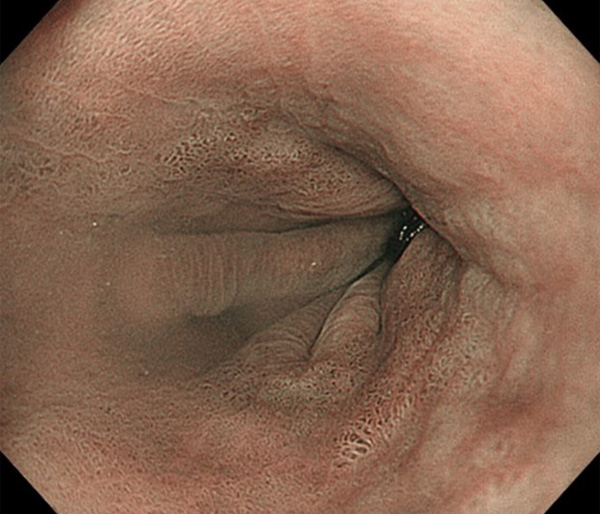

内視鏡所見と病理組織像の1対1対応が可能な症例を公募いたします。主にLSBEに発生した早期癌(HGDを含む)を対象としますが、興味深い症例であればSSBE癌でも結構です。採否は世話人へご一任ください。

症例呈示希望者は応募用紙に記入の上、代表的な内視鏡(2枚)、切除標本(新鮮、固定)、切り出し図、マッピング、代表的組織像とともに、Barrett 食道研究会事務局 barrett.shinshu@gmail.comへお申し込み下さい(10MB以下でお願い致します)。

特に、本邦では極めて稀なlong segment Barrett’s esophagus(LSBE)から発生した早期癌は、診断に難渋する場合も多く、欧米ではランダム生検による検出が標準的とされています。背景のBarrett食道もろとも全体を内視鏡切除+ラジオ波焼灼する欧米と異なり、ESDで内視鏡的な局所切除が基本の本邦では、存在診断+範囲診断(特に水平)を的確に行うことが不可欠です。

そのためには、一流の病理医による組織学的診断とエキスパート内視鏡医による拡大内視鏡像との一対一対応を徹底的に行うことで、『本来、見えないであろう拡大所見の先にある組織構築像が診えてくる』所まで内視鏡診断レベルを上げていく必要があります。その実現には、一対一対応を追究した症例(特にLSBE発生例)1例でも多く経験するしかありません。本研究会でBarrett食道腺癌(LSBE発生早期病変)を共に学び、拡大内視鏡像の一歩先を診るスキルを習得しましょう!一人でも多くの皆様のご参加をお待ちしています。